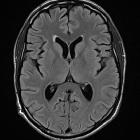

Ependymitis granularis sounds far more worrying than it actually is. The term refers to symmetrical foci of periventricular high T2 and FLAIR signal hyperintensity anterior and lateral to the frontal horns. It is just an anatomical variant, usually small, less than 1 cm, and has a triangular morphology extending laterally from the callosal genu. Pathologic lesions tend to be larger and demonstrate corresponding low signal intensity in T1WI.